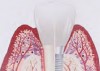

The entry of inflammatory cell infiltrate into the connective tissue (Figure 1 and Figure 2) differentiates peri-implantitis from peri-implant mucositis.1 Unlike a natural tooth—where periodontal fibers, transepithelial fibers, and gingival fibers absorb this exudate—none of these fibers are present around an implant (Figure 3). This allows the inflammatory cell exudate to directly enter the bone, resulting in bone loss and concomitant soft-tissue loss (Figure 4).1

Fig 3. Unlike a natural tooth, an implant does not have periodontal fibers, transepithelial fibers, or gingival fibers to absorb the exudate around it.

Figure 3